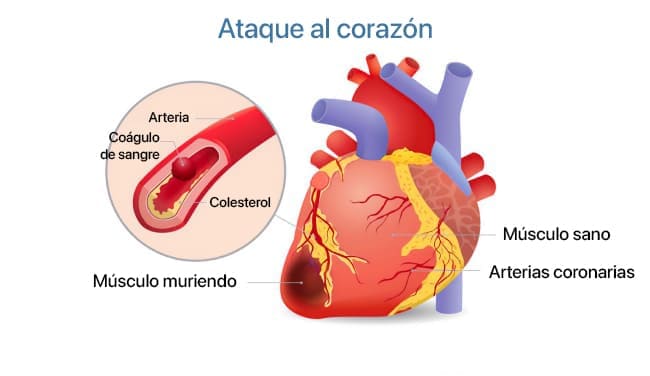

Masa trombótica

Los coágulos de sangre suelen pesar mucho menos de lo que se podría esperar, generalmente entre 800 gramos y 1 kg. Su principal peligro radica en su inestabilidad. En cualquier momento, un trombo (un coágulo de sangre) puede desprenderse y viajar por el torrente sanguíneo, lo que podría provocar bloqueos potencialmente mortales.

Si un trombo es lo suficientemente grande, puede obstruir completamente un vaso sanguíneo, cortando el suministro de sangre al órgano que nutre. Esta condición se conoce como isquemia.

Un accidente cerebrovascular isquémico ocurre cuando se bloquea un vaso sanguíneo en el cerebro. Un infarto de miocardio, o ataque cardíaco, ocurre cuando hay una obstrucción en una arteria coronaria del corazón. Otros órganos también pueden verse afectados por la isquemia. Por ejemplo, bloqueos en el hígado pueden llevar a isquemia hepática, mientras que bloqueos en los pulmones y los riñones pueden provocar fallos en estos órganos. Las hemorroides, de hecho, son una forma de isquemia vascular que afecta la región rectal. Por último, si los vasos sanguíneos de las piernas se bloquean, con el tiempo puede producirse la muerte de los tejidos, una condición conocida como gangrena.